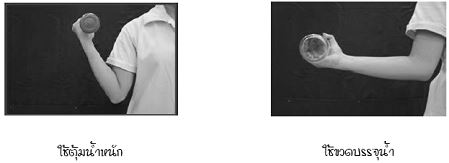

16 กันยายน 2557 04:39:26 #2 ความจริงคุณน่าจะปรึกษาคุณหมอที่รักษาอยู่ เพราะรู้พยาธิสภาพและสามารถให้คำแนะนที่เหมาะสม อย่างไรก็ดี ขอแนะนำวิธีการบริหารดังนี้ครับ การบริหารเพื่อเพิ่มองศาการเคลื่อนไหวของข้อมือ ดังนี้ การบริหารเพื่อเพิ่มความแข็งแรงของข้อมือ แขน และมือ ดังนี้ 1. เหยียดข้อมือและนิ้วมือเต็มที่ 2. กำมือและเกร็งกล้ามเนื้อมือและแขน 3. ดันมือและแขน ให้ประสานมือทั้ง 2 ข้าง ใช้มือข้างหนึ่งดันออก ส่วนมืออีกข้างหนึ่งดันเข้า เป็นการต้านแรงมือตนเอง ทำสลับข้างกัน 4. ยกน้ำหนัก เริ่มจากน้ำหนักน้อยๆ แล้วเพิ่มน้ำหนักมากขึ้น